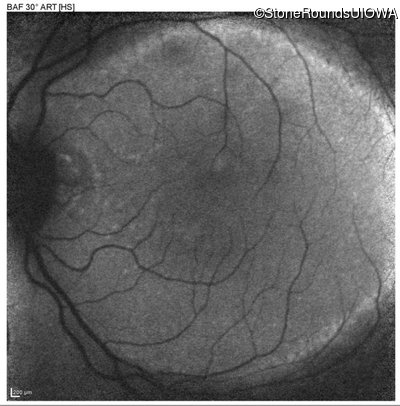

Enhanced S-Cone Syndrome (IA2fiv)

Age at visit: 45 years

This 45 year old man has had poor night vision since at least age 2 years.

The clinical features supporting the diagnosis of the enhanced S-cone syndrome (ESCS) in this patient include: stable night blindness since at least the second year of life, normally sighted parents, nummular pigment in the mid-periphery of the fundus that stops abruptly at the temporal arcades and disorganization of the retinal layers (seen on OCT) anterior to the temporal arcades.

Enhanced S-Cone Syndrome NR2E3 IVS1-2 A>C Arg311Gln CGG>CAG AR